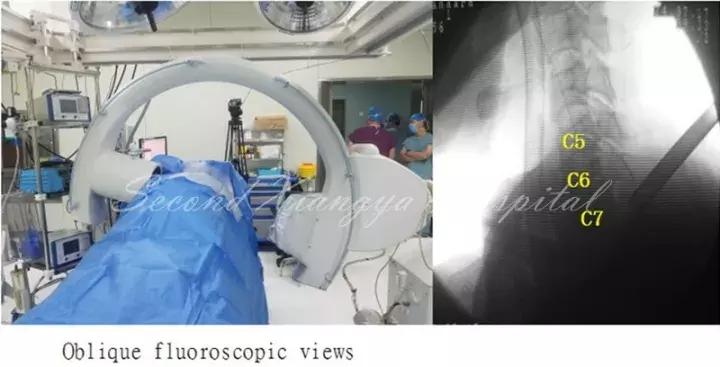

颈椎前路:与腰椎相比,颈椎由于毗邻结构复杂,穿刺风险相对较高,尤其在前路进行经皮内镜手术时更为明显。鉴于在颈椎开展经皮内镜脊髓神经损伤“零容忍”,穿刺时应特别注意技巧,即“气管投影,两指技术,皮触骨面,侧透避深。”术中透视时需找到气管侧方投影位置,然后用中指和无名指将血管鞘和内脏鞘推挤开,直至皮肤触及骨面,在两指之间穿刺入椎间隙后需透视证实未进入椎管,以确保脊髓安全。

同时,侧位透视时应调整C-Arm角度,也可通过C臂聚焦来显露被肩胛骨遮挡的下颈椎区域,从而帮助准确定位手术节段和防止穿刺后工作套管置入过深。